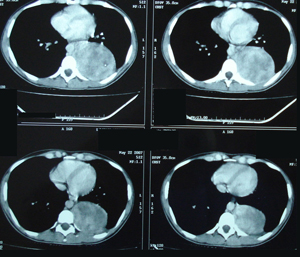

Εικόνα 3 α-δ

Αξονική τομογραφία του θώρακος. Επιβεβαιώνει τα ευρήματα της ακτινογραφίας του θώρακος. Δείχνει μάζα μαλακών μορίων, με νεκρώσεις, στο οπίσθιο μεσοθωράκιο χωρίς σημεία διήθησης παρακείμενων οργάνων.

A-B

Γ-Δ